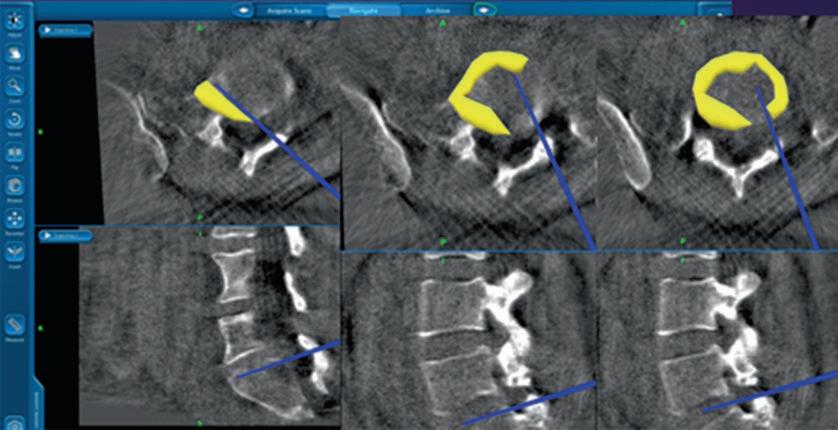

计算机辅助脊柱手术(CASS)是一门使用新的基于计算机的技术的学科,包括立体定向、导航手术和机器人技术。导航辅助脊柱手术是一组技术,它允许外科医生在手术中获取与手术器械相关的实时、三维和虚拟的脊柱图像。